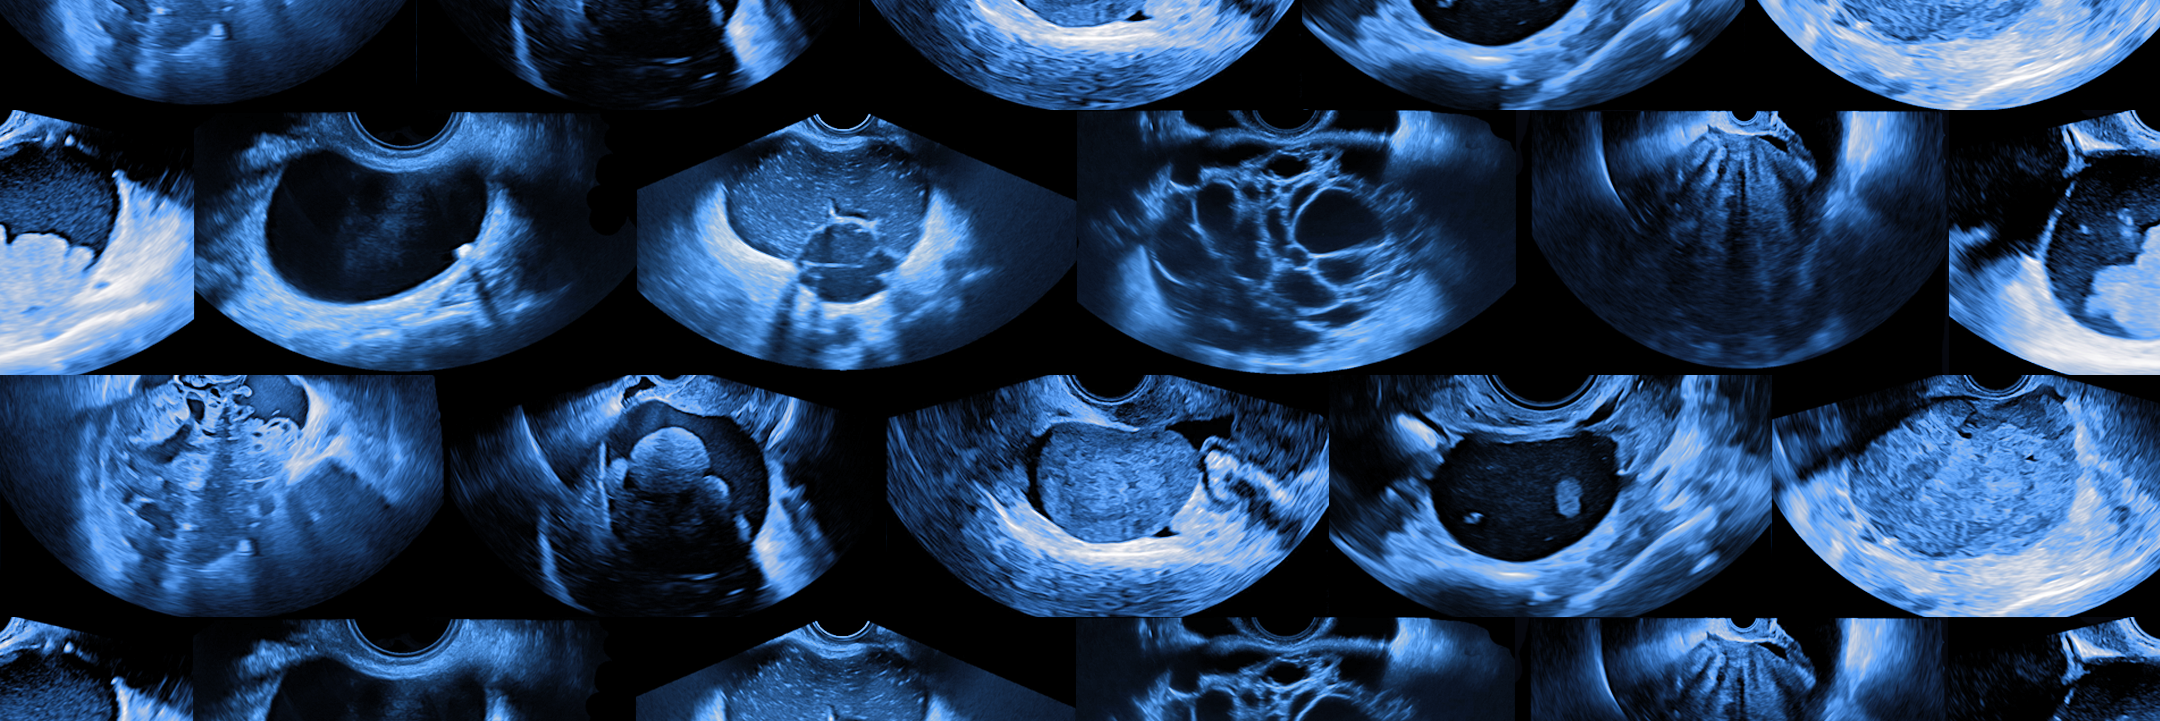

TRACE4OC™ provides the woman's level of risk of being affected by ovarian cancer from US imaging

TRACE4OC™ is our AI-based, CE-cleared medical device that uses machine learning to deeply analyze US images of adnexal ovarian masses of women at risks to provide the individual level of risk (very low risk or medium-high risk) of being affected by ovarian cancer.

The tool operates through a semi-automatic reading of the woman’s ovarian mass, obtained from a transvaginal US image frame, without contrast medium, in combination with CA-125 measure and the current woman’s menopausal state.

TRACE4OC™ identifies US-image features specifically associated to abnormal morphometric and echogenic pattern within and near an ovarian adnexal cancer mass caused by the ovarian cancer disease. Then, it analyzes these features through machine learning to automatically provide the woman’s risk and support specialists in gynecology in the diagnostic process.